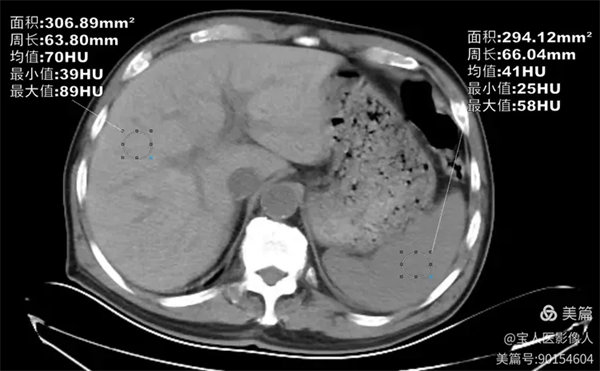

CT軸位,肝形態(tài),大小正常,而CT值約70HU,較正常肝實(shí)質(zhì)密度增高。